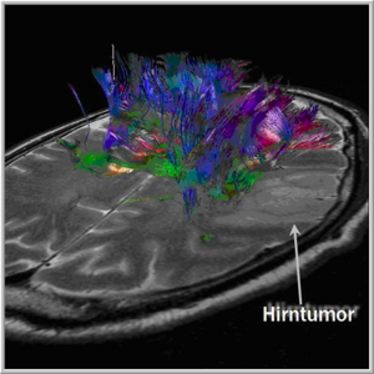

Science Day 2010

Science Day 2010